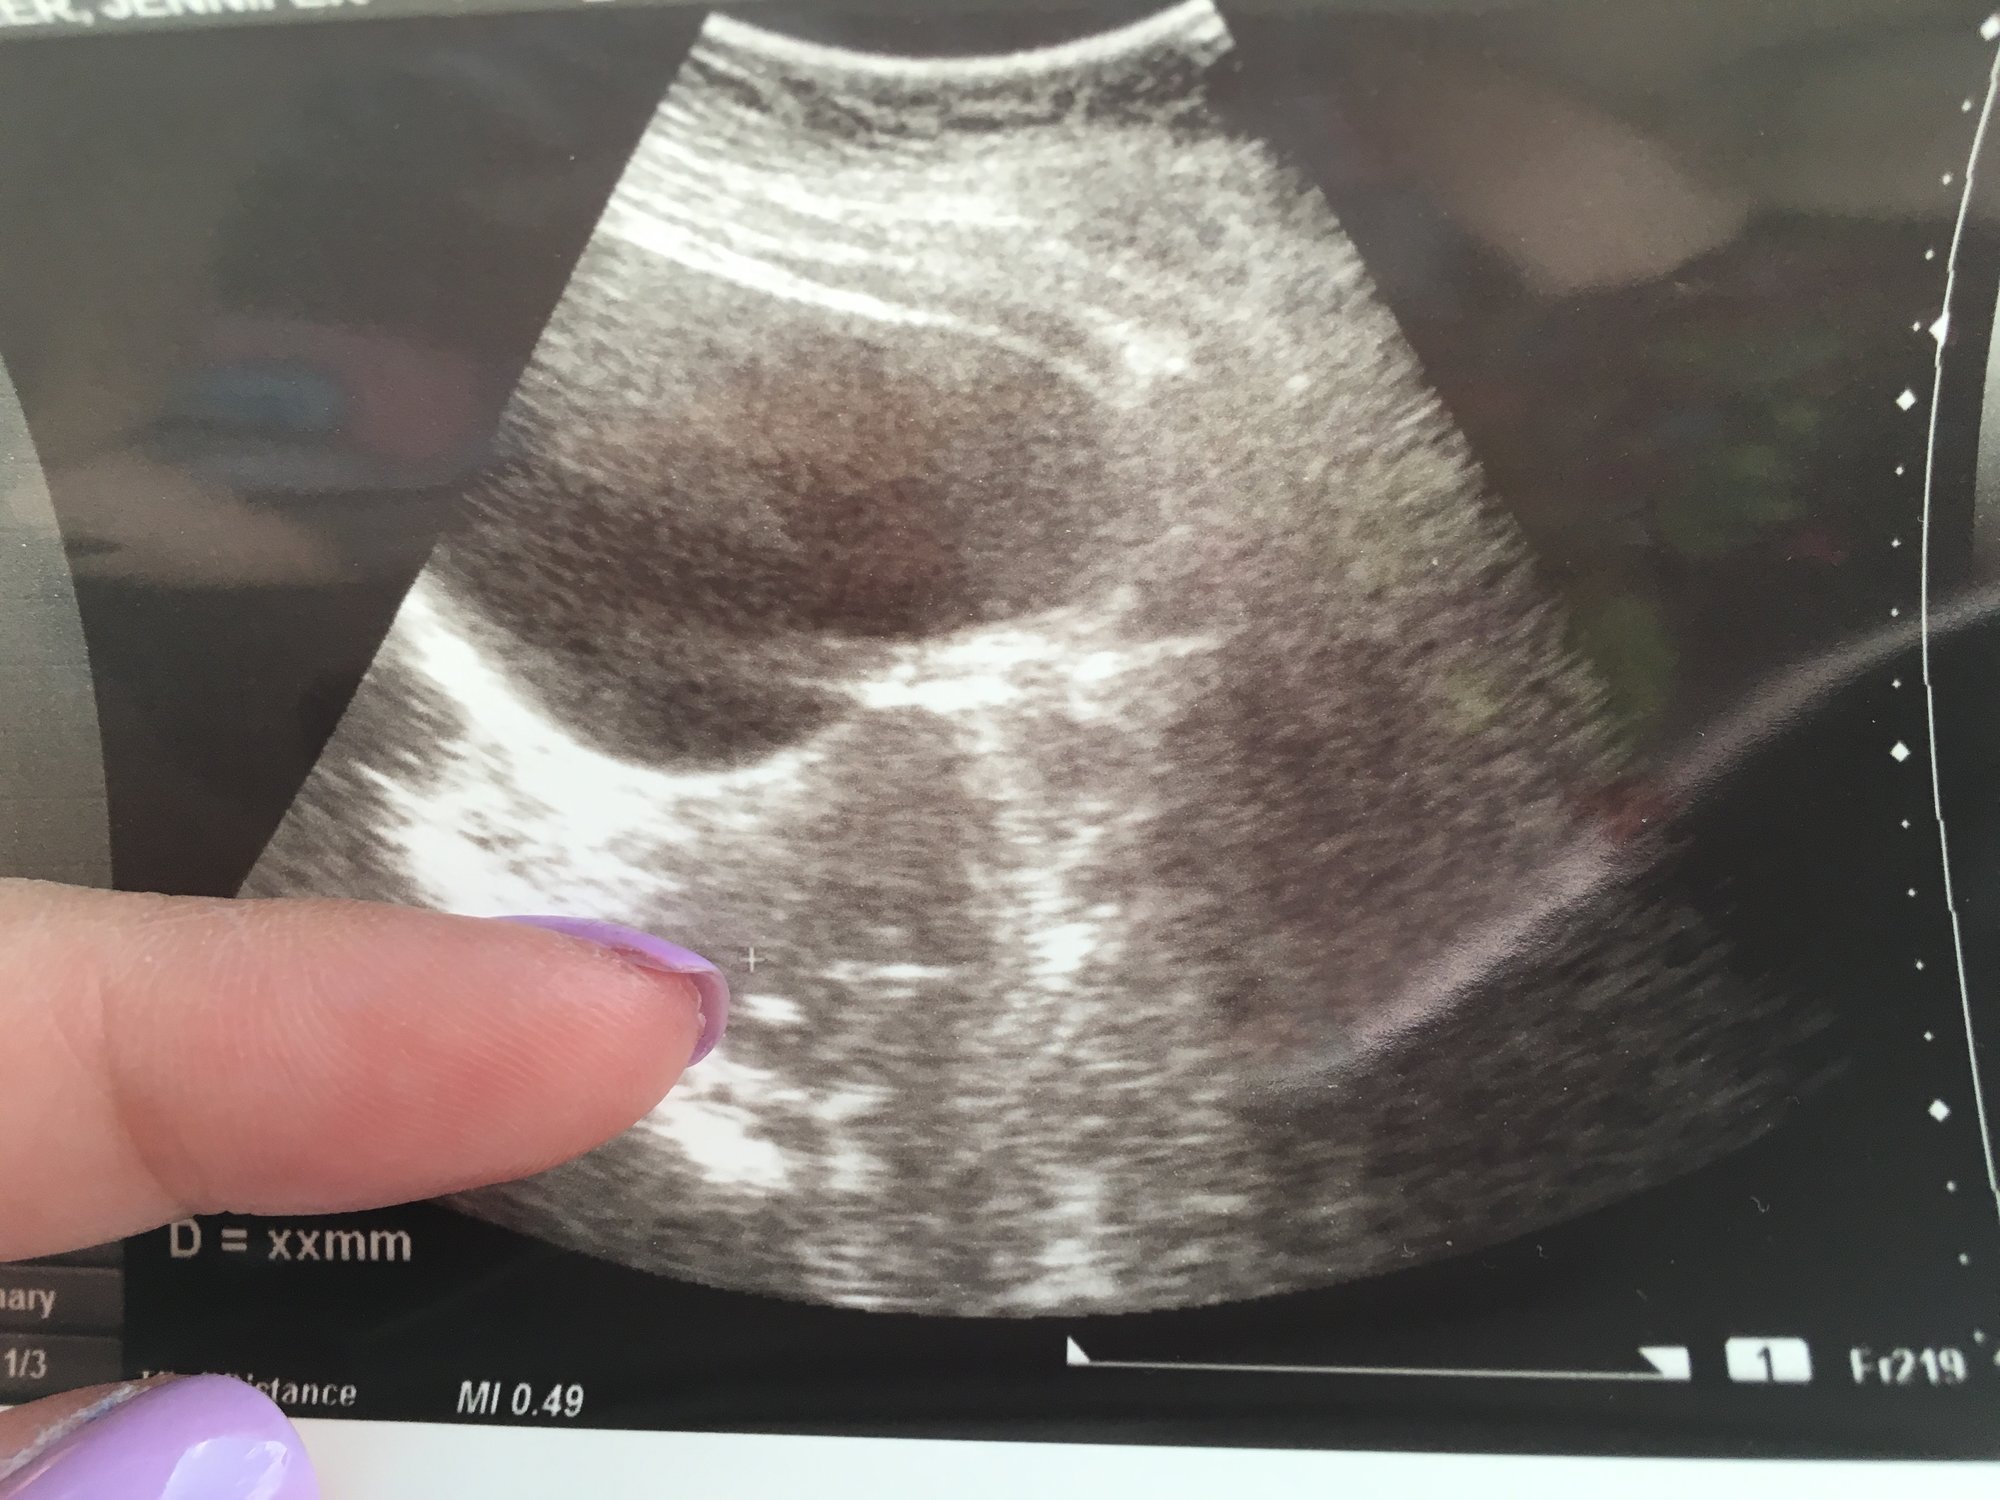

US on 7/5 1 baby found EDD 2/24/18